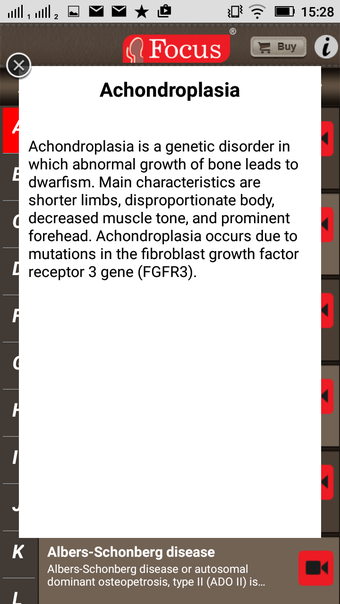

该应用程序是一本包含100个与风湿病相关的术语和定义的词典。定义以简单易用的格式呈现,辅以3D动画和视频。该应用程序分为两个部分:第一部分与医疗状况有关,第二部分与治疗和用于治疗状况的药物有关。

该应用程序是一本包含100个与风湿病相关的术语和定义的词典。定义以简单易用的格式呈现,辅以3D动画和视频。该应用程序分为两个部分:第一部分与医疗状况有关,第二部分与治疗和用于治疗状况的药物有关。